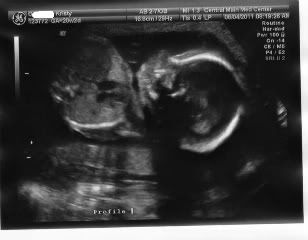

a very healthy baby. Here are some pictures from my A/S this morning. Still Team Green although the tech said the baby was very eager to show the goods. We looked away!

Here is peanut's profile